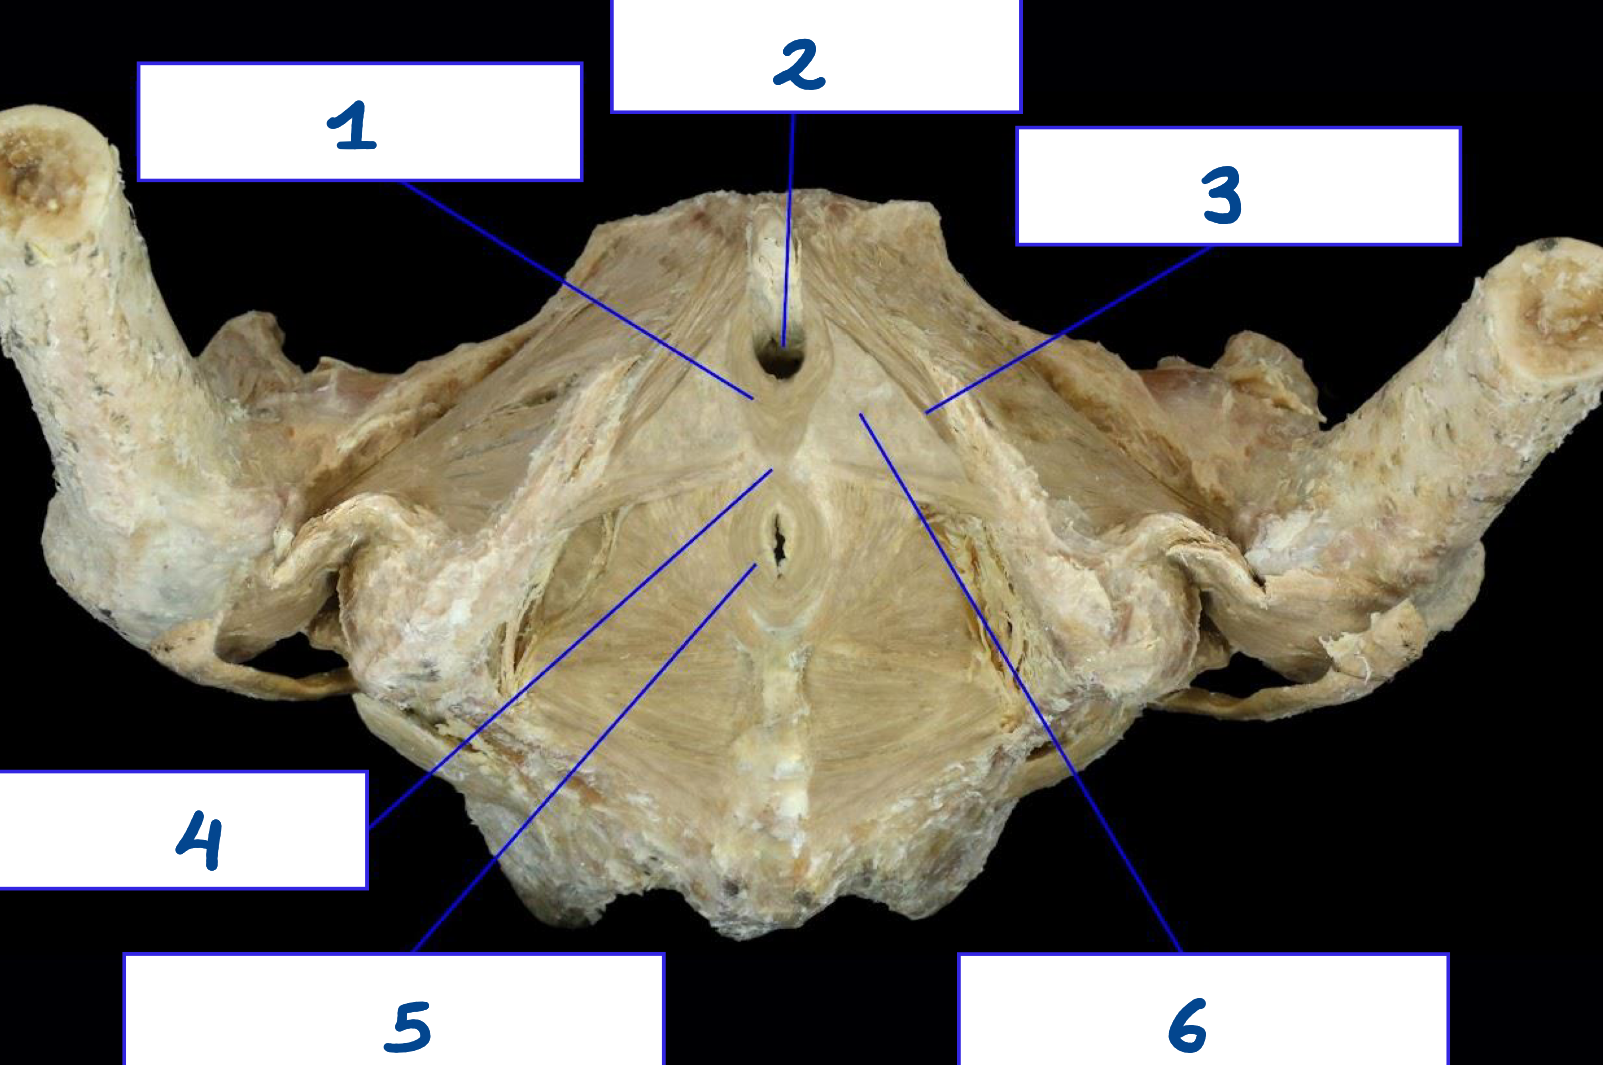

<p>What is structure 1?</p>

What is structure 1?

Superficial perineal muscle

<p>What is structure 2?</p>

What is structure 2?

Puborectalis muscle

<p>What is structure 3?</p>

What is structure 3?

Pubococcygeus muscle

<p>What is structure 4?</p>

What is structure 4?

Perineal body

<p>What is structure 5?</p>

What is structure 5?

External anal spincter

<p>What is structure 6?</p>

What is structure 6?

Coccygeus muscle

<p>What is structure 7?</p>

What is structure 7?

Iliococcygeus muscle